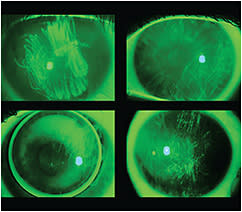

Foreign Body Tracking One of the few corneal complications that actually occurs beneath a corneal contact lens is foreign body tracking (a.k.a. foreign body staining). This is perhaps the single most common complication seen in individuals wearing corneal contact lenses. It occurs when a foreign particle finds its way beneath the lens, resulting in what patients often refer to as a “contact lens attack.”

With blinking, the foreign body rakes across the surface epithelium, resulting in a localized or diffuse corneal staining pattern (Figure 2). The foreign body is frequently self-expelled from beneath the lens by the rather significant reflex tearing induced by the semi-trapped foreign body. Because the residual defect frequently involves only the surface epithelium, the defects heal within hours, often without lens removal. Though relatively benign, these “contact lens attacks” are a frequent nuisance to corneal contact lens wearers. CLS